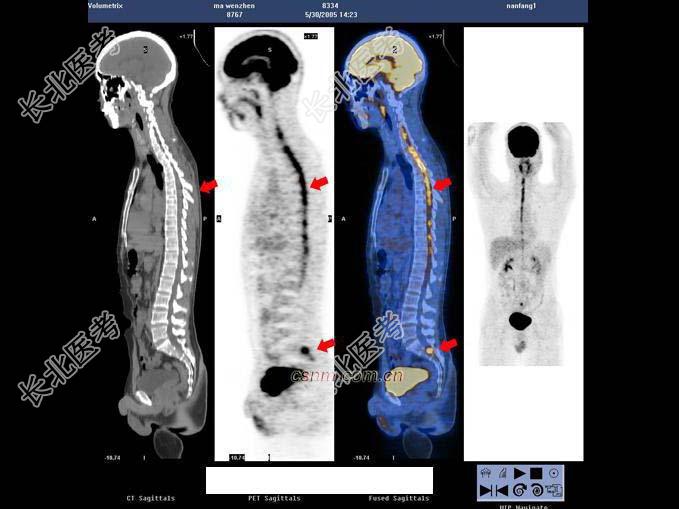

- 多项选择题男,32岁, 确诊左颞叶胶质母细胞瘤Ⅳ级,手术切除病灶, 术后放疗2个月,化疗3个疗程; 现距放疗结束17个月。查体:右上肢轻度乏力, 骶尾部及双足麻木,排便困难; 检查:MRI示左颞叶肿瘤局部复发可能。行PET/CT显像全身检查如图。最可能的诊断是 ( )

A、马尾种植性转移灶

B、恶性肿瘤沿椎管种植性转移

C、左侧颞叶术后瘢痕组织改变

D、左侧颞叶肿瘤复发